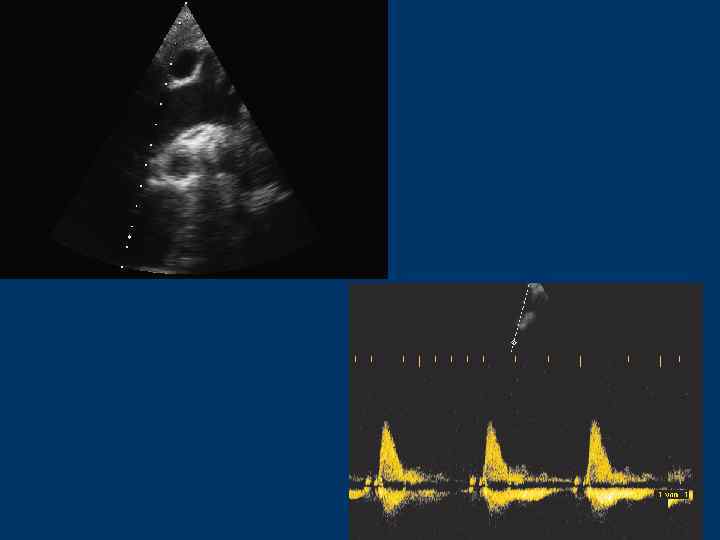

Аортальный клапан и выносящий тракт ЛЖ (LVOT) • Парастернальная позиция по длинной оси ЛЖ • Апикальная 5 -камерная позиция • Апикальная 3 -камерная позиция

Трансаортальный поток

Выносящий тракт ЛЖ (LVOT): Контрольный объем – в выносящем тракте ЛЖ под створками АК Аортальный клапан: Контрольный объем – между створками АК или в аорте не ниже 1 см

Скорость потока через АК - 1, 35 м/с (1, 0 -1, 7) Скорость потока в ВТЛЖ – 0, 9 м/с (0, 7 -1, 1)

Выносящий тракт ЛЖ Скорость потока 0, 8 -1, 2 м/с